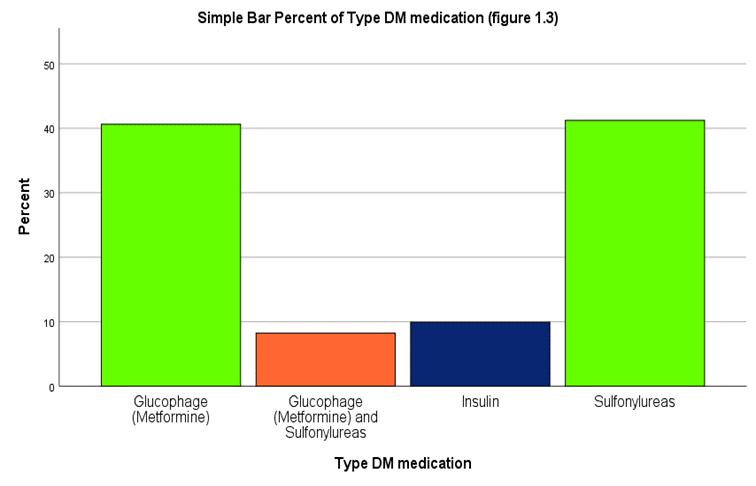

Safety and Efficacy of Conventional Antithrombotics versus Direct Oral Anticoagulants in Diabetic Patients: A Jordanian-based cross-sectional study

The prevalence of diabetes mellitus (DM) is rapidly improving and leads to metabolic disease and severe complications. This study assessed...Read More